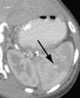

Intrasplenic hematoma